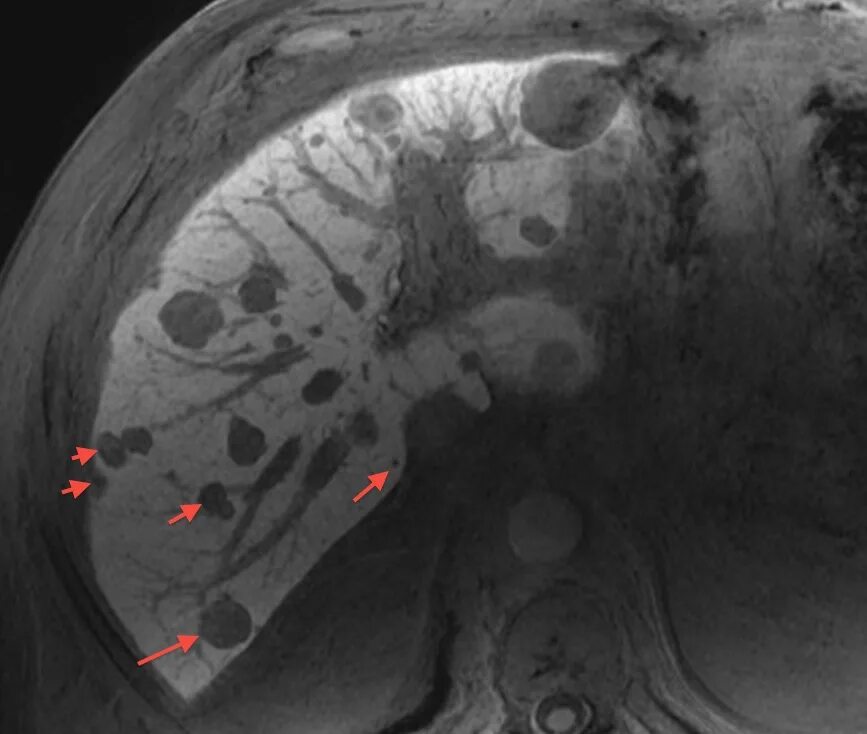

Вероятность метастаз